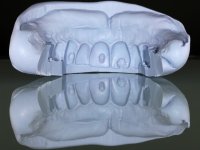

Realizada uma TAC, foi planificada a colocação de 6 implantes no maxilar superior. Foi decidida a colocação de dois implantes na zona dos incisivos centrais, dois implantes na zona dos caninos e dois na zona dos segundos pré-molares. A ausência de estrutura óssea na zona distal do primeiro quadrante implicava a realização de uma regeneração óssea no seio maxilar direito. A cirurgia foi realizada e após a colocação dos implantes foi feita a impressão para confeção de uma prótese provisória metalo-acrílica aparafusada para colocação em carga imediata no dia seguinte. O implante colocado na zona do seio maxilar direito não foi colocado em carga. Passados 6 meses foi realizada a impressão aos 6 implantes com técnica de moldeira aberta e foram confecionados os modelos de trabalho. Numa consulta seguinte foram montados os modelos de trabalho em articulador semi-ajustável utilizando o arco facial e a relação inter-maxilar obtida com a prótese provisória. Foi feita uma muralha de silicone sobre a ponte provisória com o objetivo de orientar o trabalho laboratorial. Realizada a infra estrutura metálica aparafusada esta foi provada em boca e finalmente após colocação de cerâmica o trabalho foi colocado definitivamente. Como passaram vários meses após a realização da primeira TAC foi feita uma segunda para planificar a colocação de implantes no 4º quadrante. Colocaram-se 3 implantes na mesma sessão em que foi feita a extração dos pilares da ponte. Estes implantes foram posteriormente reabilitados com uma ponte metalo-cerâmica aparafusada de três elementos.